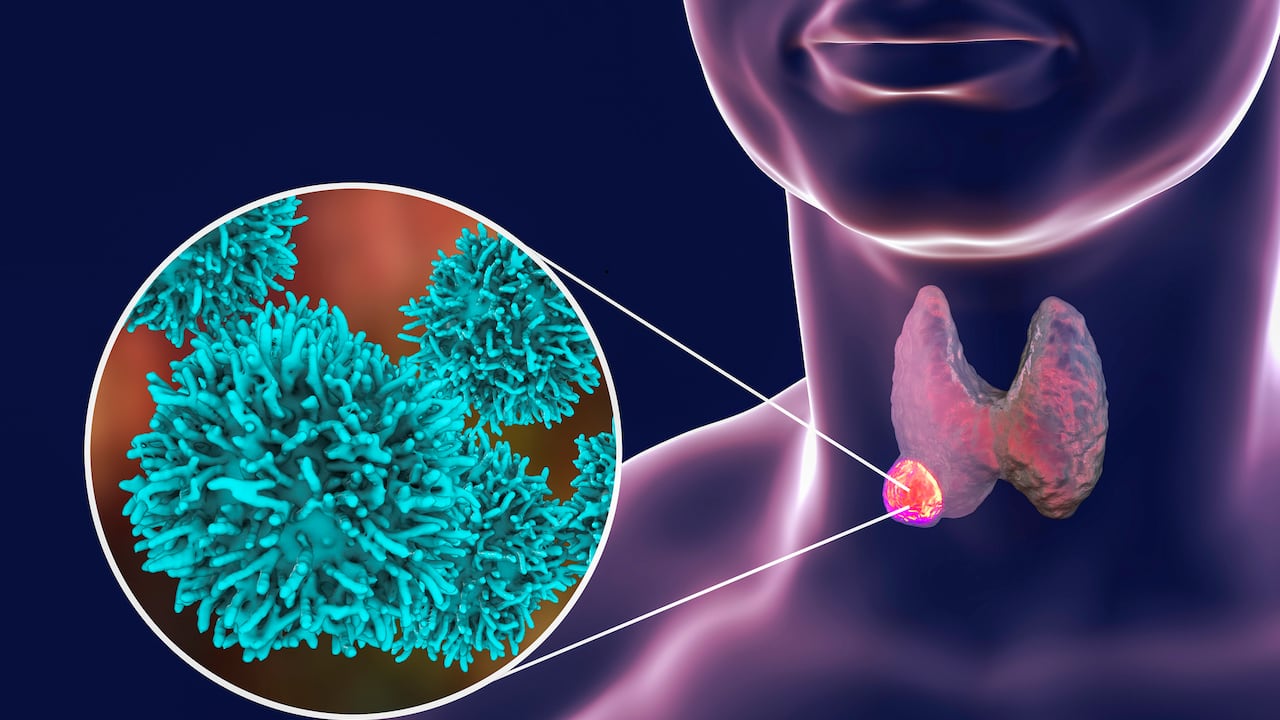

El cáncer de tiroides es un tipo de cáncer que se origina en la glándula tiroides, una hormona que ayuda a regular el metabolismo, la frecuencia cardíaca, la presión arterial y la temperatura corporal. Normalmente, las personas que tienen entre 25 y 65 años y son mujeres, tienen mayor riesgo de padecer esta enfermedad.

De acuerdo con el portal Manual MSD, este cáncer tiene cuatro tipos, entre ellos el papilar, que es el más frecuente y representa el 80 % de todo los tipos de cáncer de tiroides. Como tal, este cáncer crece dentro de la glándula tiroidea, pero a veces se extiende (metastatiza) a los ganglios linfáticos adyacentes. Si no se trata, puede propagarse a zonas más distantes.

Cuando se identifica el cáncer de tiroides, se producen pequeños tumores (nódulos) en el interior que son malignos y se caracterizan por ser un tumor sólido en vez de estar lleno de líquido (quístico), no produce hormona tiroidea, es duro, crece con rapidez y se asocia a ganglios linfáticos engrosados y dolorosos en el cuello.